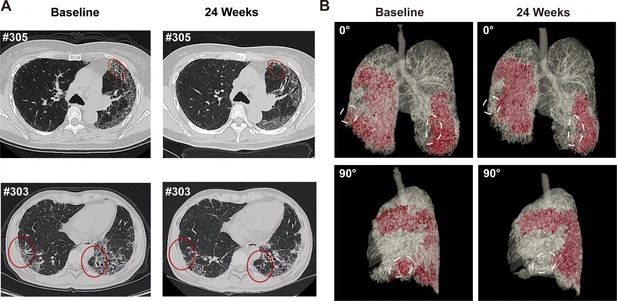

- 蜂窩狀病變消退:1M劑量組中兩名患者(#303、#305)的HRCT顯示下葉蜂窩狀病變減少(圖4A),三維重建證實(shí)下葉病變區(qū)域縮小(圖4B)。

(A) 患者#305和#303在基線和REGEND001治療后24周的代表性肺部CT圖像。紅色圓圈表示蜂窩狀病變消退。(B) 患者#305連續(xù)CT圖像的三維可視化。紅色區(qū)域表示細(xì)胞治療前后肺部受損區(qū)域(網(wǎng)狀和蜂窩狀)。白色圓圈表示下葉病變消退。

總結(jié):REGEND001高劑量治療可顯著改善IPF患者運(yùn)動能力及生活質(zhì)量,并在部分患者中實(shí)現(xiàn)肺纖維化結(jié)構(gòu)的可逆性修復(fù)(尤其下葉)。療效呈現(xiàn)劑量依賴性,且與細(xì)胞分布機(jī)制相關(guān)。盡管樣本量有限,但結(jié)果為再生療法逆轉(zhuǎn)肺纖維化提供了首個影像學(xué)證據(jù),需擴(kuò)大隊(duì)列驗(yàn)證長期效果及機(jī)制。